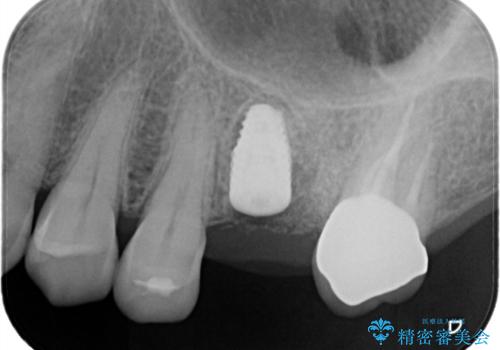

抜歯後、骨増生を行ったのちインプラントを埋入しています。